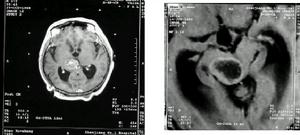

3.CT掃描:不但可定位,並可顯示腫瘤的大小、形狀及腦組織、腦室的改變、特別易於發現多發性腫瘤、腫瘤類圓形或形狀不規則,呈高密度或混雜密度影像,混雜密度者常為腫瘤內有壞死囊變,則顯示有低密區。強化後大多有明顯的塊狀或環狀影像增強、腫瘤周圍常有低密度腦水腫帶。可見腦室受壓變形,小腦腫瘤可見第三腦室以上對稱擴大。

顱內壓增高症狀明顯,局限體徵較重一般情況較差者,應首先考慮本病。由於腦轉移來自肺者多見,應照肺像。如肺像發 現腫瘤,或有其他部位惡性腫瘤史者,診斷一般可以確立。 進一步確診需作特殊檢查。CT掃描對定位定性以及發現多發腫瘤,診斷價值最高。